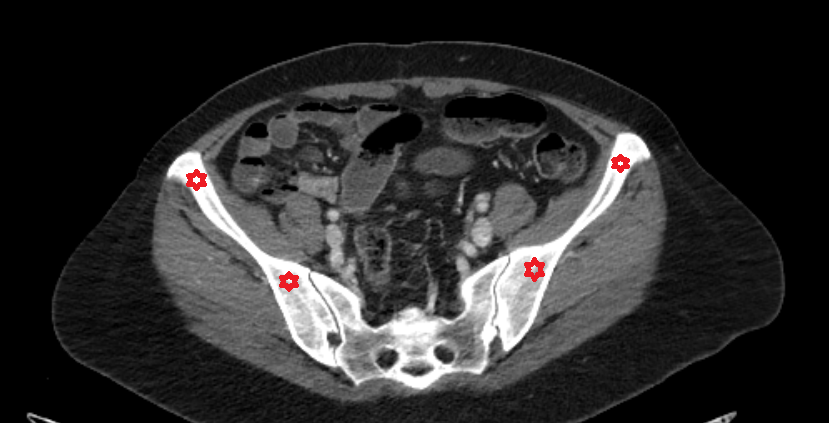

- External iliac artery

- Internal iliac artery

- External iliac vein

- Femoral vein

- common iliac artery

- Ala of ilium (wing of ilium)

- Sacroiliac joint

- Sacrum